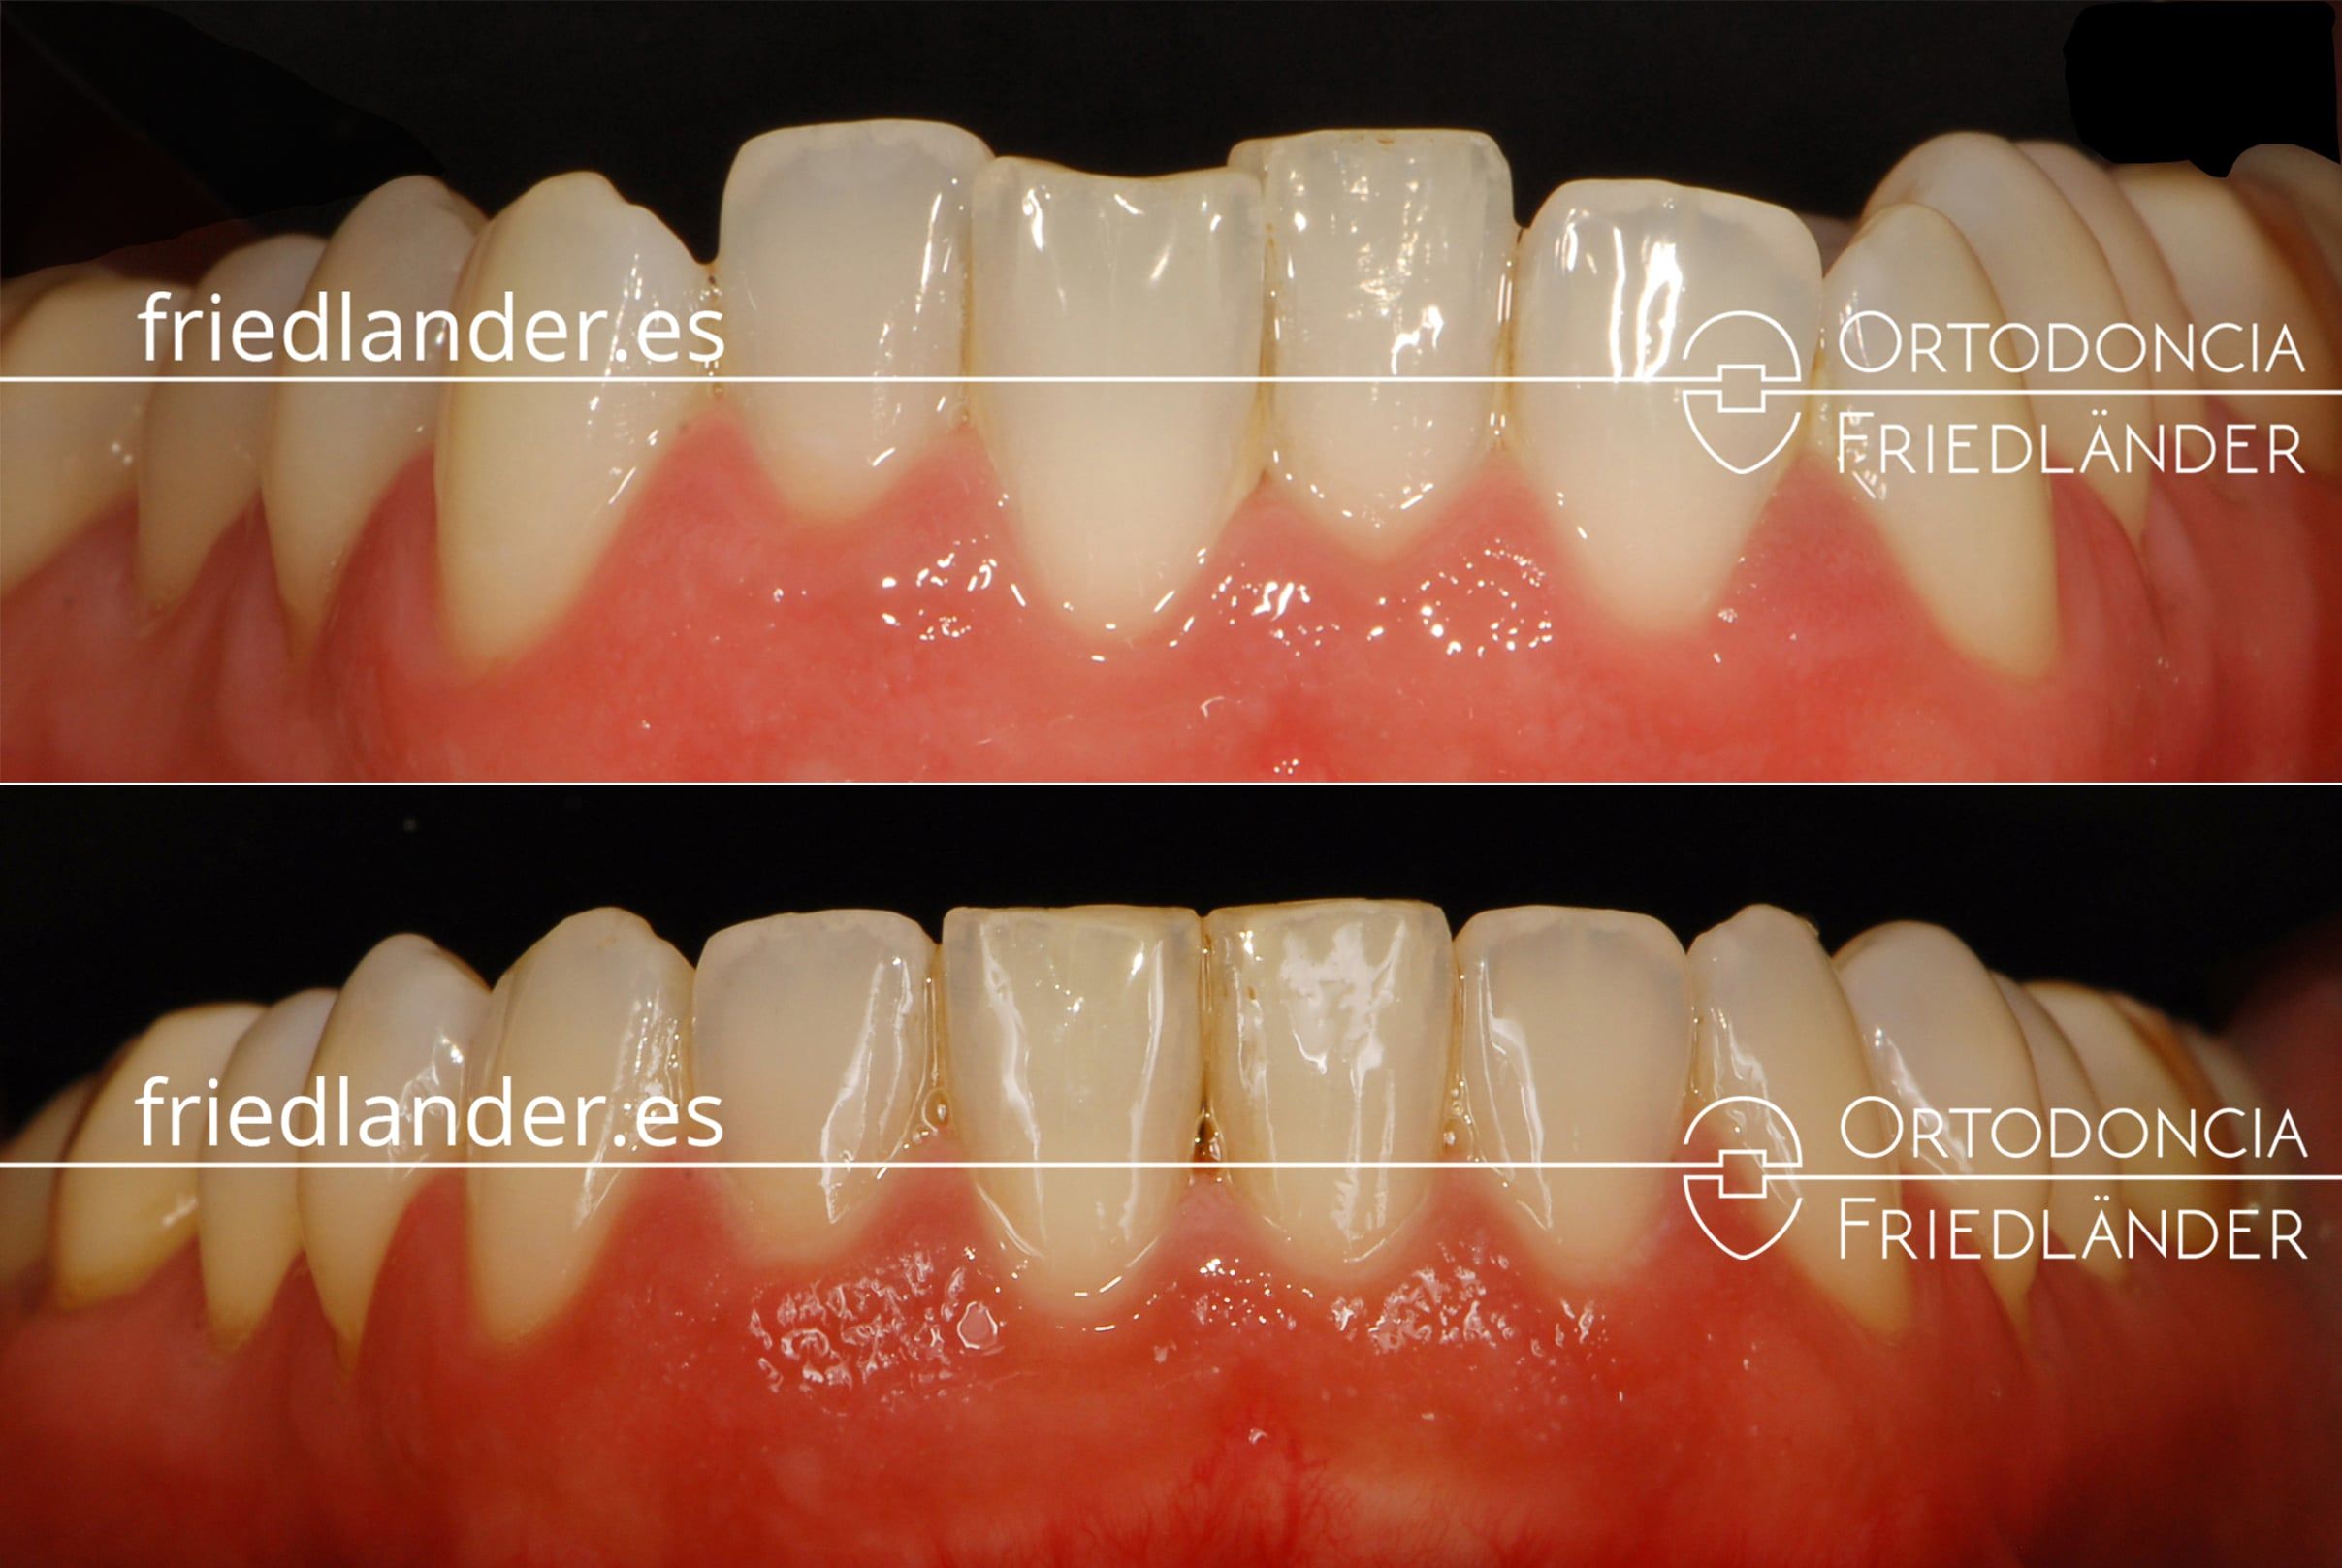

Detalle de la nivelación de los dientes inferiores